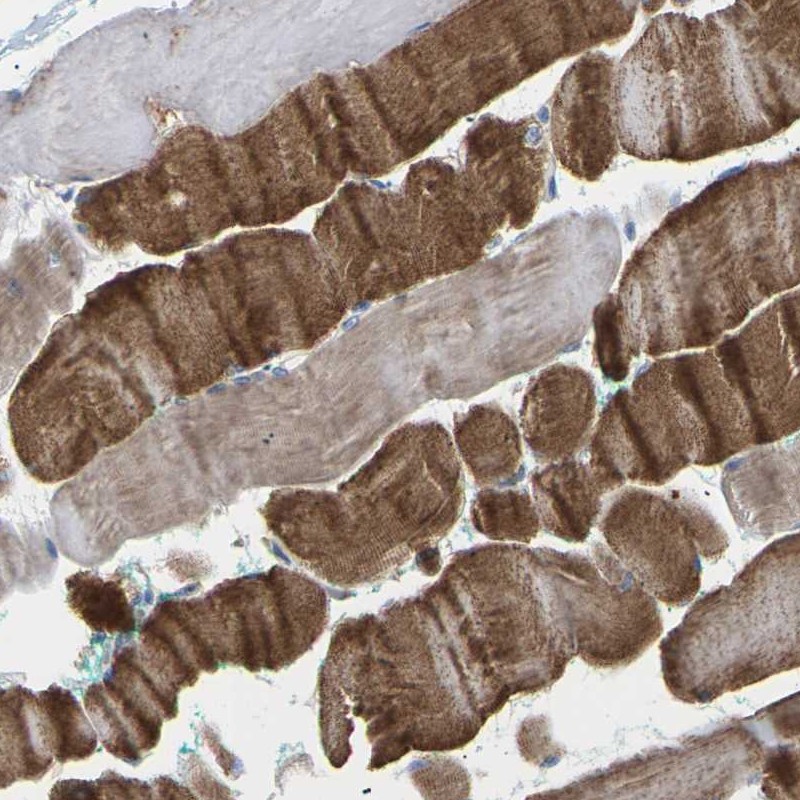

Immunohistochemical staining of human skeletal muscle shows strong cytoplasmic positivity in myocytes.